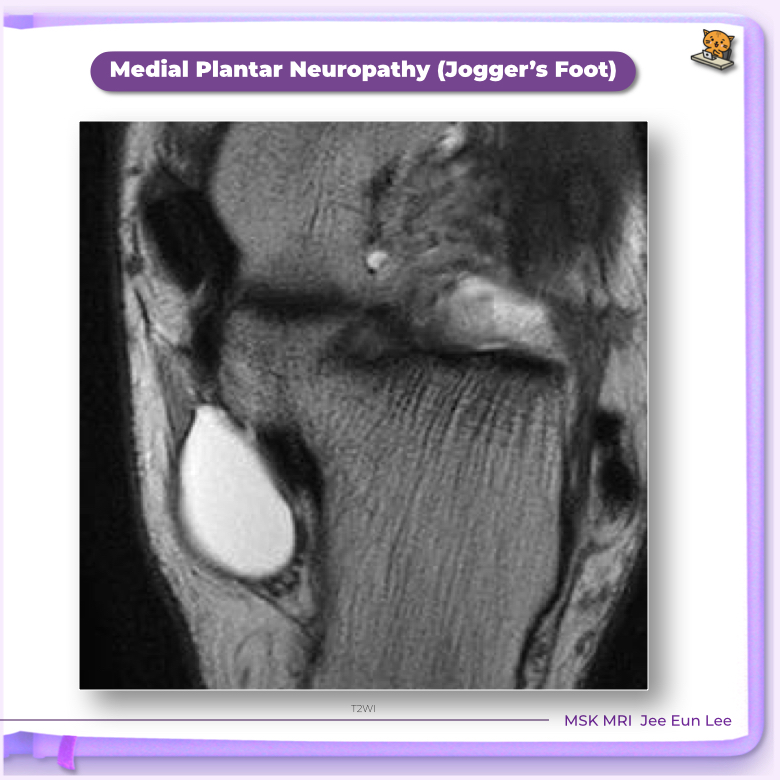

• MR:

Edema or atrophy of the abductor hallucis and flexor digitorum brevis muscles, with sparing of abductor digiti minimi